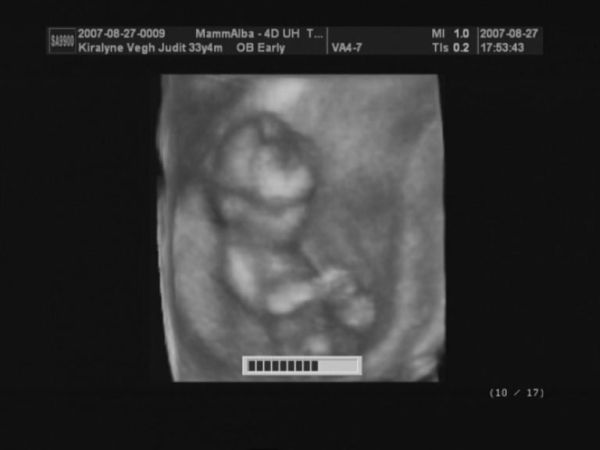

4D képek

Kép

Nagyon édes a babó,nagyon szépen látszik a képeken!!!!!

És olyan de olyan helyes kismanó van a pocidban!! :lol:

Nagyon édes a baba a képeken(szerintem csajszi lesz,olyan szép!! :wink: )

gyönyörűek vagytok mindnyájan! Az egyik képen mintha szopná az ujját, miközben hátonfekszik keresztbe tett lábbal és feje alatt a másik keze ("napozik", 2D-s kép oldalról) :lol: